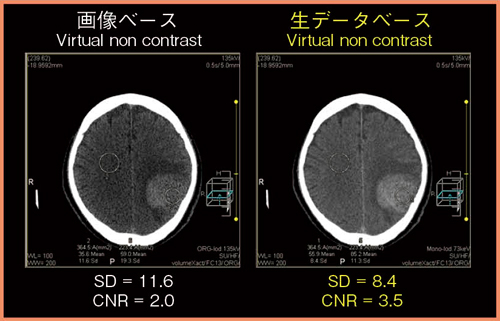

仮想非造影画像について,画像ベースと生データベースの画像を比較した(図7)。生データベースでは画像ベースよりもノイズが低減されており,SDは11.6に対し8.4と改善した。また,CNRも2.0から3.5に向上した。

図7 仮想非造影画像の比較